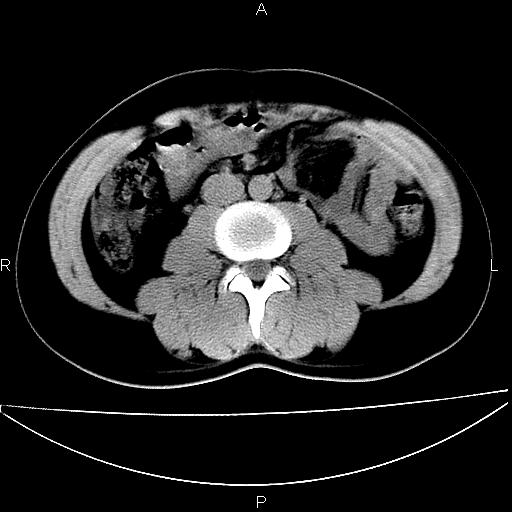

男 25岁 自述 尿频尿急,排尿困难20多天.无腰痛, b超说左肾盂轻度积水,左输尿管上端扩张.未见结石影. ct我看双侧肾盂轻度积水,双输尿管上端都扩张,大家看看能看见结石吗?

考虑肾外肾盂 前列腺轻度肿大 密度欠均 考虑炎性改变

肾外肾盂,必要时+c